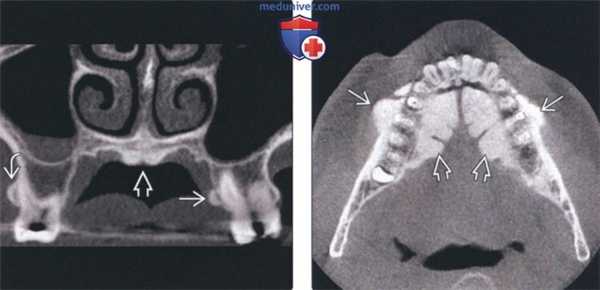

(Слева) На аксиальной КЛКТ визуализируются большие фестончатые рентгеноконтрастные разрастания, представляющие собой нижнечелюстные валики.

(Справа) На корональной КЛКТ определяется сдавление языка огромными нижнечелюстными валиками. Валики покрыты тонкой слизистой оболочкой, которая может травмироваться. При хроническом воспалении или нарушении функции валики удаляются. Обратите внимание на верхне и нижнечелюстные щечные экзостозы, которые часто сочетаются с нижнечелюстными валиками.

(Слева) На периапикальной рентгенограмме определяются едва заметные рентгеноконтрастные участки возле шеечного края передних зубов. Эти выбухающие участки, чаще возникающие на нижней челюсти, носят название щечной «губы». Клинические они выглядят как маленькие бугорки под нормальной слизистой оболочкой.

(Справа) На аксиальной 3D КЛКТ визуализируются множественные экзостозы с щечной стороны верхней челюсти в области моляров и премоляров. Столь многочисленные экзостозы можно удалить, т.к. они способны привести к функциональным нарушениям. Видна также щечная «губа» в передних отделах верхней челюсти.

4. КТ при щечных и небных экзостозах челюсти:

• КЛКТ:

о Экзофитные участки внешне не измененной костной ткани возле альвеолярного гребня

(Слева) На корональной КЛКТ определяются щечный и небный экзостозы в задних отделах верхней челюсти. Небный экзостоз иногда называют верхнечелюстным валиком. Обратите внимание на маленький небный валик, который часто появляется вместе с экзостозами.

(Справа) На аксиальной КЛКТ определяются множественные щечные экзостозы в области премоляров нижней челюсти Присутствуют также выбухающие нижнечелюстные валики. Частота экзостозов наивысшая при наличии нижнечелюстного и небных валиков одновременно.